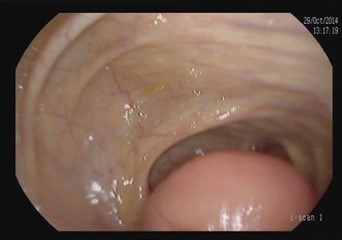

Figure 1: Endoscopic visualization of appendiceal mucocele.

Appendiceal mucinous neoplasm accounts for 8-10% of appendiceal tumors and nearly 58% of malignant appendiceal tumors. LAMN is a borderline or low-grade malignant tumor, regardless of rupture, and is characterized by implantation metastasis [2-4]. Its pathogenesis involves atypical hyperplasia of the glandular appendix epithelium that obstructs the appendix with a gradual accumulation of mucus resulting in increased pressure. Mucus penetrates the muscularis mucosa and produces mucinous masses around the appendix and in the retroperitoneum [9-12]. Most cases are asymptomatic, and in the absence of acute infection, the symptoms and signs of LAMN resemble those of chronic appendicitis [13]. In our series, we observed and grouped the cases as patients treated only with appendectomy (5 patients) and as patients treated with cecal resection or Right Hemicolectomy (RH) (13 patients). It is important to underline that, in our experience, some patients underwent more extensive surgery for advanced disease. In fact, we performed surgery with peritoneal cytoreduction and Hipec in 7 cases. As other Authors reported in their analysis, we had similar data at pathology specimen as median size of primary tumour was 4.5 cm and surgical margins after colonic resection were free of tumor in all cases. A correct diagnosis of appendiceal neoplasm may be difficult, but on physical examination large tumors can be found as a complete oval mass with no surrounding adhesions [10]. An appendiceal mucinous cyst that forms from an appendiceal lesion can easily be misdiagnosed as a common appendiceal abscess or right adnexal cyst. In terms of resectability criteria for appendiceal mucoceles, the decision to perform an appendectomy versus a more extensive procedure, such as right hemicolectomy, is guided by several key factors [14-16,21]. Studies have shown that tumors confined to the distal appendix without cecal involvement can be managed with a simple appendectomy, while those extending to the appendiceal base or demonstrating high-grade features require a cecal resection or right hemicolectomy to achieve clear margins and reduce recurrence [5,16]. Additional evidence indicates that involvement of the mesoappendix or adjacent structures increases the risk of mucin spillage and subsequent pseudomyxoma peritonei, warranting more aggressive surgical intervention [6,11,20]. These criteria, along with tumor size and the possibility of lymphatic spread, although rare in lowgrade lesions, are central to intraoperative decision-making. In the study of Rauwerdink et al. [13] it is observed that AMN histology does not always reflects its associated PMP grade, while PMP grade strongly influences survival. By carefully assessing these factors, surgeons can determine the most appropriate extent of resection and thereby optimize patient outcomes. Abdominal ultrasound and CT or MRI are auxiliary diagnostic methods that can distinguish appendiceal mucinous cysts from other lesions before surgery [18,19]. CT is a more accurate imaging method for the diagnosis of appendiceal neoplasms, and shows a cystic mass closely adjacent to the cecum, with a round or long tubular shape, thin wall, and a smooth and regular outline. When CT shows an irregular cyst wall and thick soft tissue, it is more likely to be malignant. MRI performed with a variety of sequences and scanning methods, and high tissue resolution can clearly and consistently distinguish the wall and fluid of the appendiceal mucinous cyst, and more accurately show the integrity and boundary of the cyst wall. In this case, additional MRI evaluation showed typical manifestations of appendiceal cysts [16,19]. Recently in a clinical study, Guaglio et al. [5] observed that if LAMN had been radically resected with appendectomy, even with limited peritoneal spread, it recurred unlikely; furthermore, appendix wall perforation and the presence of mucin, cells, or both outside the appendix did not carry a higher risk of metachronous peritoneal dissemination. Moreover, in the study of Young et al. [6] were analyzed patients with positive surgical margin or perforated neoplasm with mucin on the serosal surface of the appendix, but right hemicolectomy seemed to offer no additional benefit over appendectomy alone. However, Wang et al. [11] operated 159 patients with LAMN and, after a median follow-up time of 38 months, observed that 7 patients recurred and developed pseudomyxoma peritonei. These Authors stated that surgery plus Hipec was necessary for LAMN after complete removal in patients with a high risk of recurrence. At the same, Gibson et al. [3] studied 223 patients with pseudomyxoma peritonei and stated that survival was more closely associated with the grade of the peritoneal disease than with the grade of the primary neoplasm. Their findings support the developing concept that mutational analysis may provide prognostic information in patients with PMP. But, when mucin is found intraoperatively, surgeons should consider appendectomy with possible conversion to an open approach for thorough exploration. Emergency HIPEC is unnecessary during appendectomy; instead, it should be planned electively after resolution of the acute clinical situation and with the definitive histological examination. It is important to underline that in a recent study of Salminen et al. [10] the appendiceal tumor rate in patients with periappendicular abscess was 14.3%, which was higher compared with uncomplicated acute appendicitis (14.3% vs 1.5%) and complicated acute appendicitis without periappendicular abscess (14.3% vs 2.4%). Of these 54 tumors, there were 21 low-grade appendiceal mucinous neoplasms, 20 adenocarcinomas, 8 adenomas, and 5 neuroendocrine tumors. The factors contributing to the development of PMP from appendiceal neoplasm remain unclear. However, based on the results of the most recent analysis, patients with mucin on mesoappendix or neoplastic epithelium extending into muscularis propria/serosa, perforation and positive margin have a higher risk of developing into PMP [11]. Therefore, the majority of the surgeons suggested and performed cytoreduction plus Hipec on these patients.